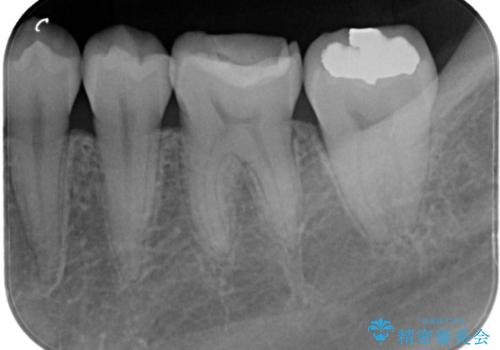

銀歯を無くしたい セラミックインレー

- 銀歯が気になるということで来院された患者様です。

セラミックでの治療を希望されたので治療をいたしました。

銀歯は長い間使用していると隙間ができて、虫歯の原因になります。

そのため適合の良いセラミックをお勧めいたします。